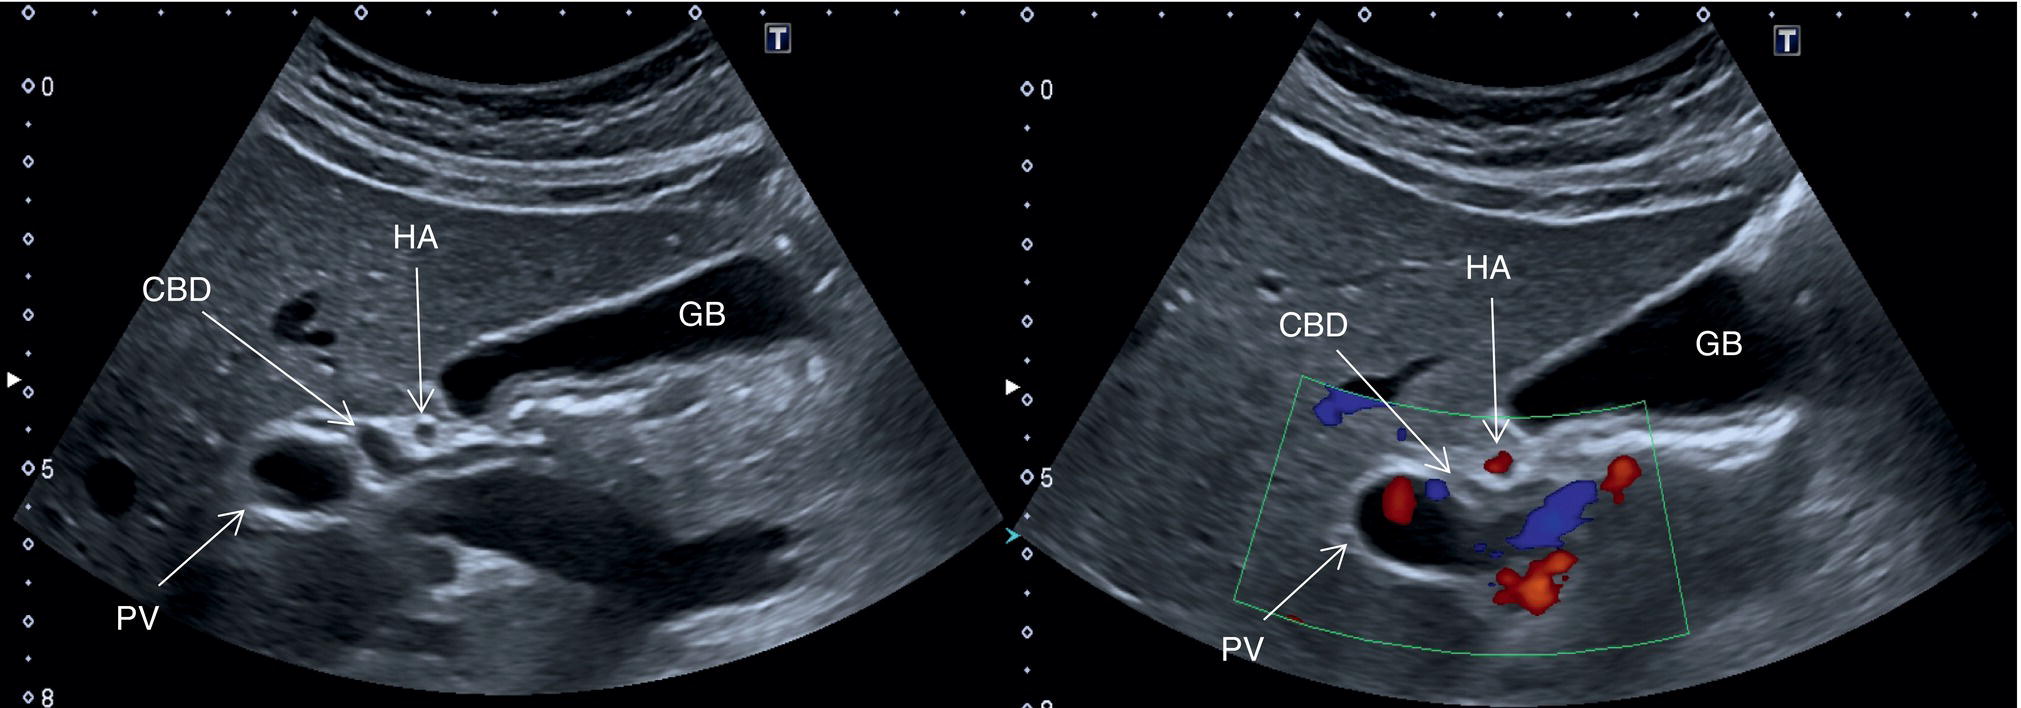

In normal physiological conditions, the CBD is the only biliary duct that can be clearly seen as a thin tubular structure with echogenic walls that in the majority of cases runs anteriorly and parallel to the PV at the level of the hepatic hilum (Figure 3.8). However, the anatomical relationship of the biliary ducts and the portal vessels may vary along their course, and usually the peripheral biliary ducts (which are only clearly visible when dilated or significantly thickened) run posteriorly to the PV (Figures 3.9 and 3.10).